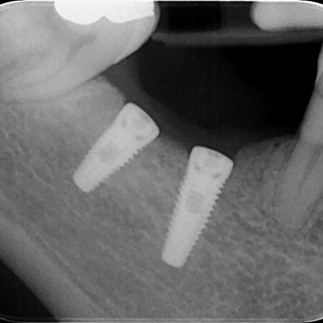

Quando gli impianti dentali vengono posizionati con tecniche "in due tempi", una volta inseriti si attendono dai 2 ai 4 mesi (in funzione della tipologia di impianto utilizzato) affinche' avvenga quel processo di guarigione denominato "osteointegrazione" in cui la fixture e l'osso alveolare si fondono. Durante questa fase viene utilizzata sulla festa della fixture una "vite tappo" o vite di chiusura (vedi radiografia sottostante). A guarigione avvenuta, l'impianto viene poi scoperto, la vite di chiusura rimossa ed al suo posto viene posizionata una vite di guarigione che ha il compito di condizionare la gengiva in modo tale che guarisca attorno ad essa, ricreando un profilo di emergenza anatomico del tutto simile a quello del dente naturale. A guarigione avvenuta dei tessuti gengivali, sarà possibile sostituire alla vite di guarigione un abutment standard o individuale, dell'altezza o del diametro corretto in funzione delle condizioni anatomiche della zona, e si prosegue con le successive fasi proteiche: